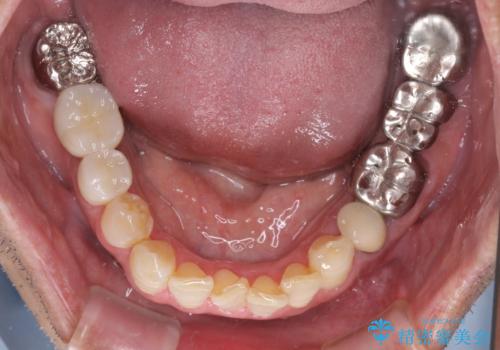

左上の奥歯は2本抜歯が必要であったため、治療期間中は右側に負担がかかり、頻繁に仮歯が壊れてしまいました。

左上に仮歯が装着されたからは咬み合わせが安定し、スムーズに治療を進めることができました。